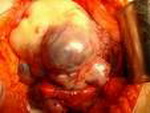

Рак яичников представляет собой злокачественное новообразование, которое берет свое начало из ткани главных половых желез женского организма.

Рак яичников – это гинекологическое заболевание, при котором в яичнике женщины развивается злокачественное новообразование эпителиального происхождения.